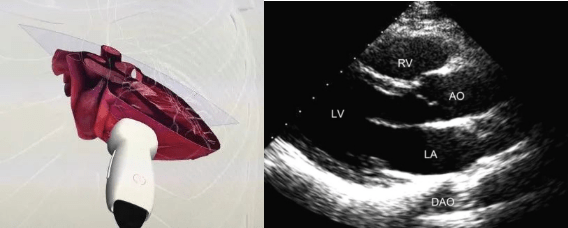

重症超声胸骨旁左室长轴切面

胸骨旁左心室长轴切面

胸骨旁左室长轴切面二维影像

1. 胸骨旁左室长轴切面